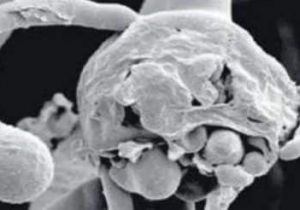

16 जिलों में ब्लैक फंगस के 1200 मरीज, अब तक 76 की मौत

27 May, 2021 04:38 PM IST | SAMIKSHASAGAR.COMभोपाल। कोरोना के संक्रमण की थमती दूसरी लहर के बाद अब ब्लैक फंगस ने हाहाकार...